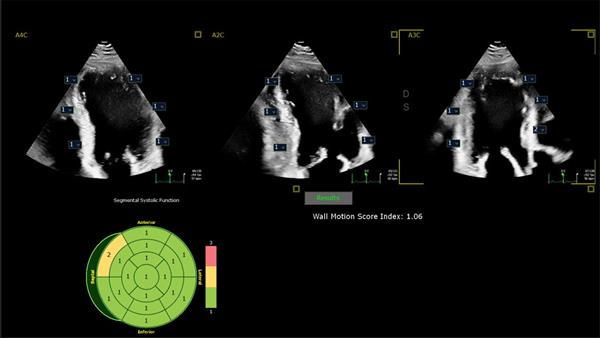

- New FDA-cleared AI-enabled applications include the industry’s first automated tool for segmental wall motion scoring of the heart to quickly and objectively identify disorders including coronary artery disease and cardio-oncology issues in seconds

Dr. Lang will join other clinicians to share the results of a new scientific abstract being presented at the American Society of Echocardiography (ASE2024) annual meeting (June 14 – 16, Portland, US), demonstrating how first-of-kind AI algorithms co-developed with Philips provide highly accurate detection of regional wall motion abnormalities (RWMA) on echocardiography. RWMAs can be an independent indicator of adverse cardiovascular events and death in patients with cardiovascular diseases like myocardial infarction (MI) and congenital heart disease. Automated machine learning-based assessment of RWMA has the potential to improve the efficiency of all readers. “An advantage of AI methods over conventional visual analysis is that it can be performed in seconds, providing rapid and accurate information to help augment expert reads by quickly highlighting areas of concern for RWMA, improving the ease and efficiency of interpretation,” Lang added.

Clinical image showing how integrating AI into cardiac ultrasound provides automated segmental wall motion scoring

- Clinical image showing how integrating AI into cardiac ultrasound provides automated segmental wall motion scoring